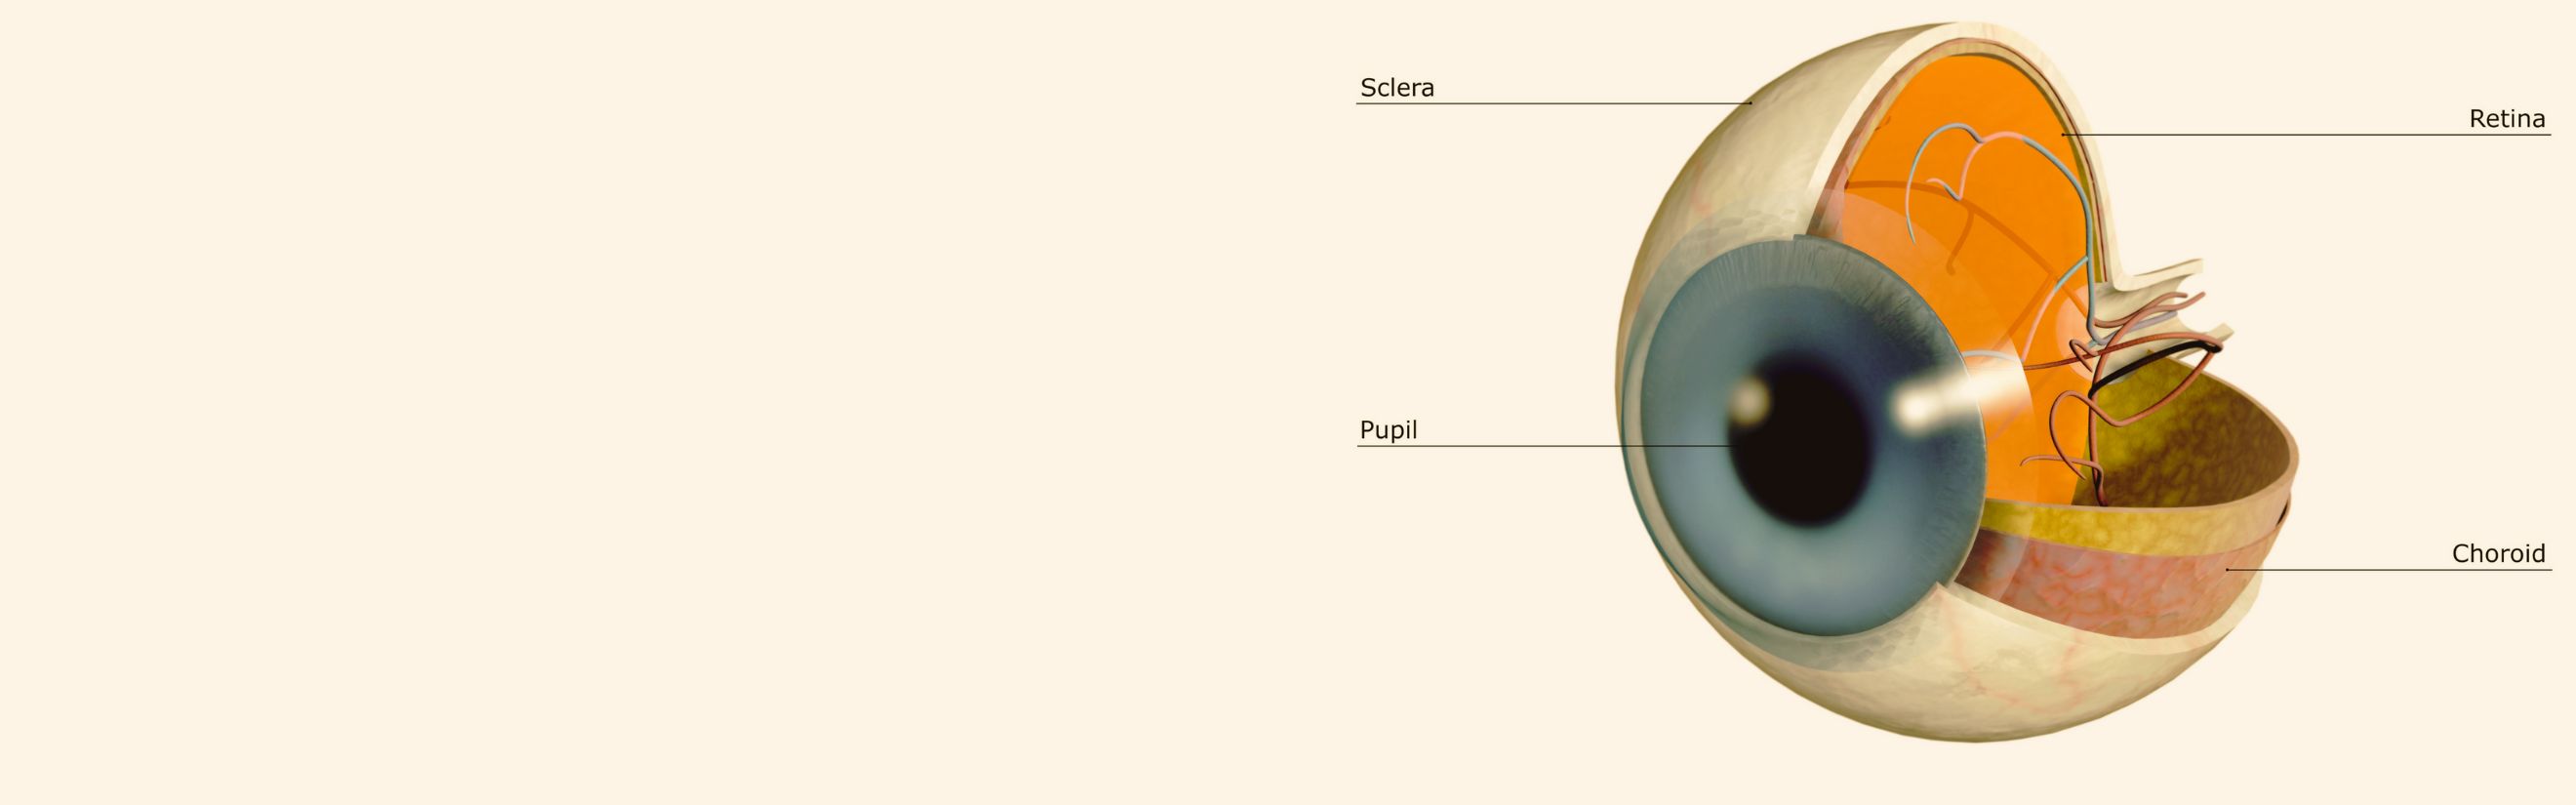

Diabetic Retinopathy |

Types of Diabetic RetinopathyThere are two types of diabetic retinopathy:

InvestigationsFluorescein Angiography

Optical Coherence Tomography (OCT) - In diabetics, OCT can “map” areas of macula edema (“swelling”) thus facilitating fluorescein angiography in guiding laser treatment of the macula. Treatment